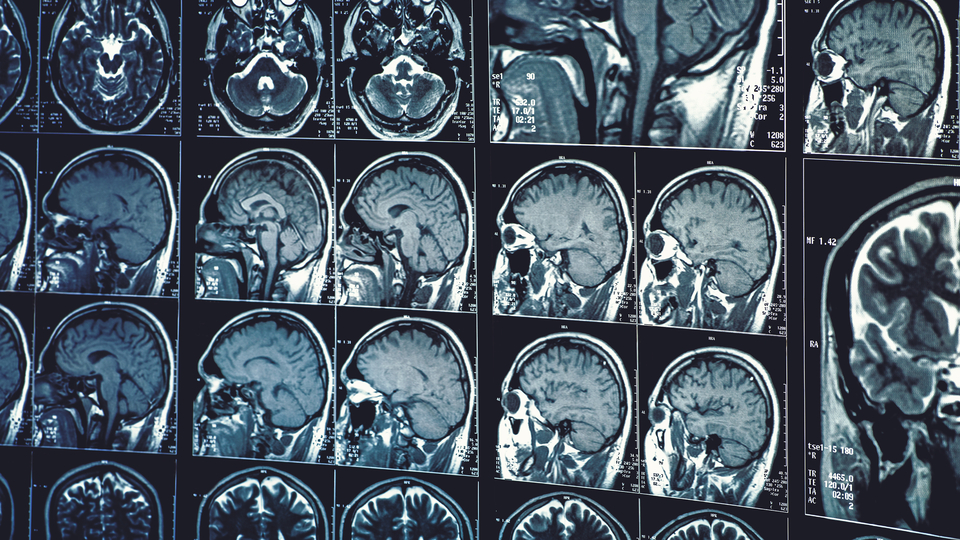

AA'nın BBC kaynaklı haberine göre, yetkililerin açıklamasında, 2022'de sadece bir kişinin hastalığa yakalandığının tespit edildiği, virüsün bulaştığı kişilerin çoğunda hastalık belirtisi olmadığı ancak hastalığın beyinde ödem oluşturabileceği bilgisi yer aldı.